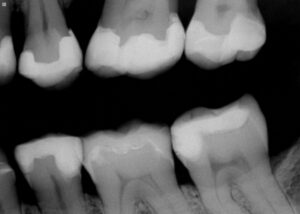

Please find attached the revised composite restoration for tooth #15/2.7 DOB retaining the mesial wall. A single shade of A3 Voco Grandio SO was used with the matrix in matrix system in place on the DOB and is slated to perform well in this high load region due to its intrinsic compressive strength of 439MPa. A post-operative radiograph is attached for reference.